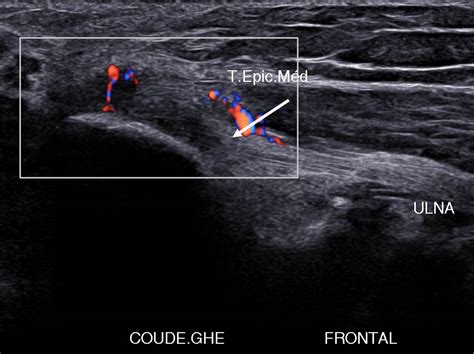

L'échographie est la technique de choix pour visualiser la lésion, évaluer son étendue, sa profondeur et la zone atteinte. Elle permet de suivre l'évolution de la cicatrisation. Dans de rares cas sévères, la radiographie peut être utilisée. L'IRM (imagerie par résonance magnétique) est l'examen de choix pour un diagnostic précis et fiable, particulièrement recommandé pour les boiteries chroniques, bien que son coût soit élevé (environ 1000€).